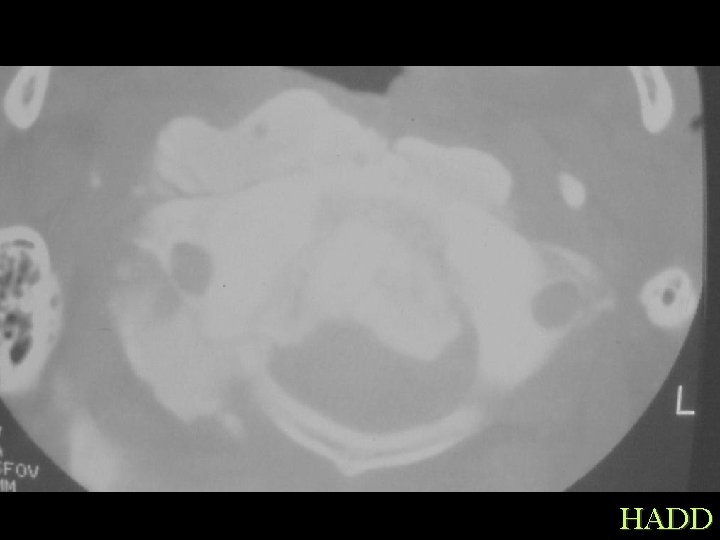

Dystrophic Traumatic HADD

Dystrophic Traumatic